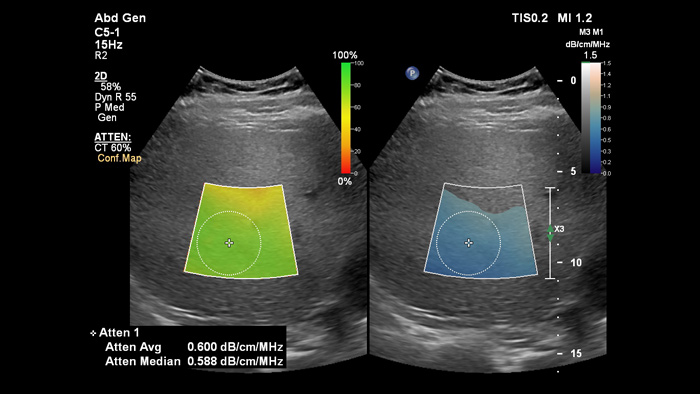

Mit Hilfe der Attenuation Imaging kann die Fettmenge in der Leber gemessen werden, indem der Abschwächungskoeffizient des vom Leberparenchym absorbierten Schalls errechnet wird. Diese Methode bietet quantitative Abschwächungsparameter, die Ärzte bei der Behandlung von Patienten mit Lebersteatosen unterstützen.

Attenuation Imaging